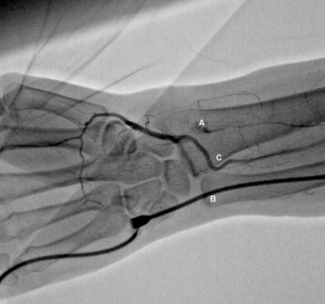

We prospectively evaluated, in a quaternary hospital, patients undergoing coronary angiography or percutaneous coronary intervention by transulnar approach, in case of failure or contraindication to the ipsilateral radial access.